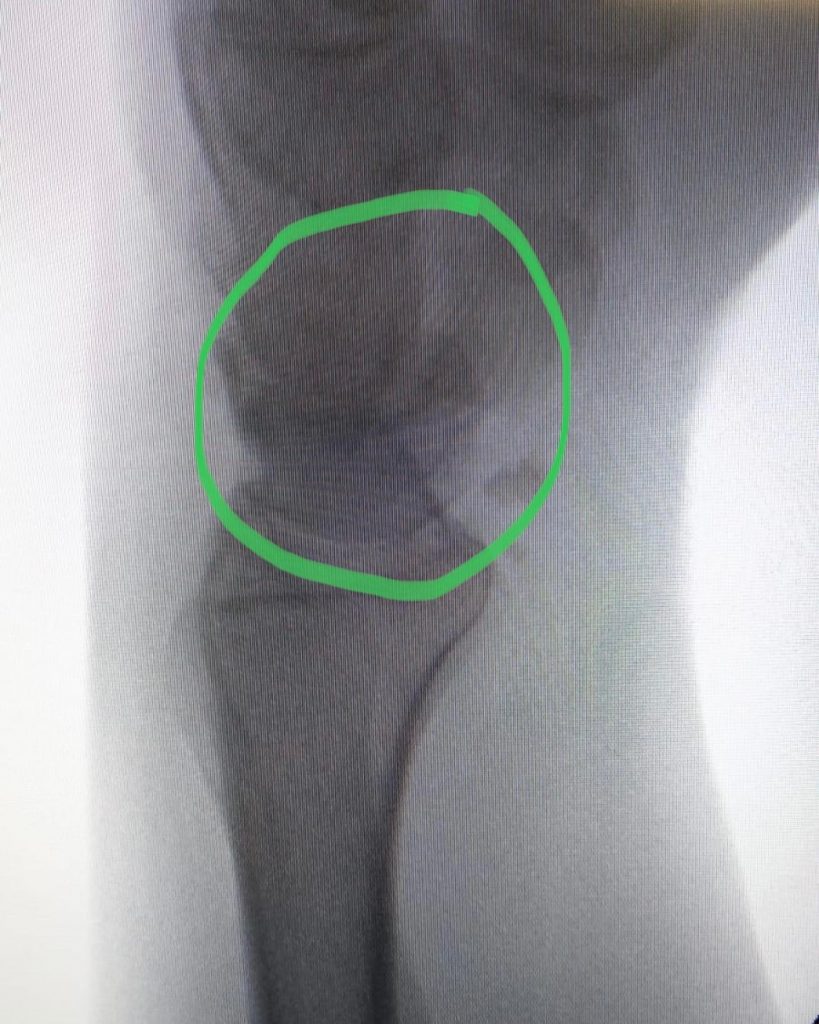

Pseudoartrose do escafóide:A pseudoartrose é uma patologia que ocorre quando não há consolidação de uma fratura após o período esperado – o osso “não colou”.

Nesses casos, é indicado intervenção cirúrgica. É uma situação comum nas fraturas do escafóide.

No caso acima, foi tratada com retalho ósseo vascularizado e fixação com parafuso de Herbert.